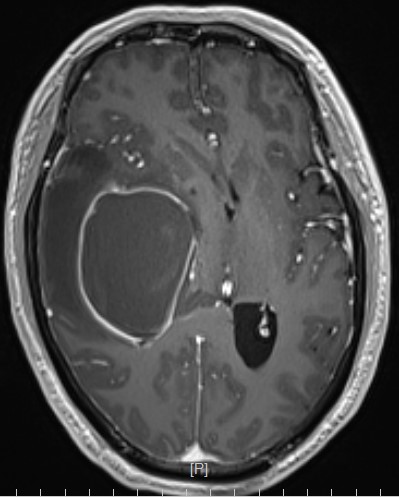

患者,男性,59岁,头痛伴四肢无力一周入院

头部MR提示:右颞叶,岛叶及基底节区巨大占位,胶质母细胞瘤可能性大